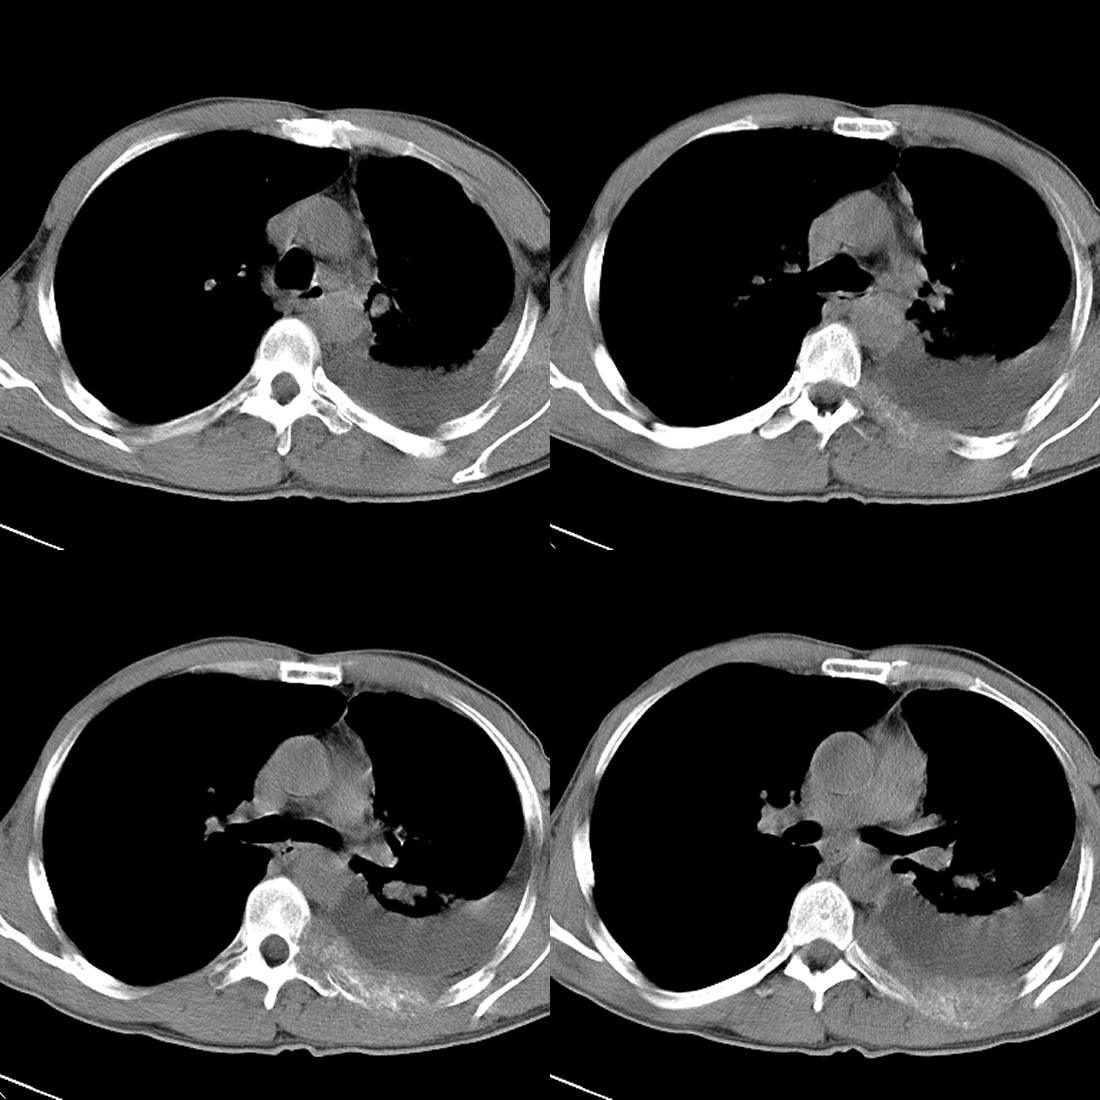

左肺上叶周围型肺癌伴肺\\胸膜\\肋骨\\胸椎横突转移,左侧胸腔积液.

左侧椎体、横突、肋骨呈溶骨性破坏,半左侧胸腔中等量积液;左肺尖部可见一肿块影,边界欠清;多考虑恶性骨肿瘤,不除外肺尖部转移性表现可能。

左肺上叶周围型肺癌伴双肺\\胸膜\\肋骨\\胸椎横突转移,左侧胸腔积液.

左肺上叶周围型肺癌伴肺\\胸膜\\肋骨\\胸椎转移。

左肺上叶周围型肺癌伴肺胸膜肋骨胸椎横突转移,左侧胸腔积液。